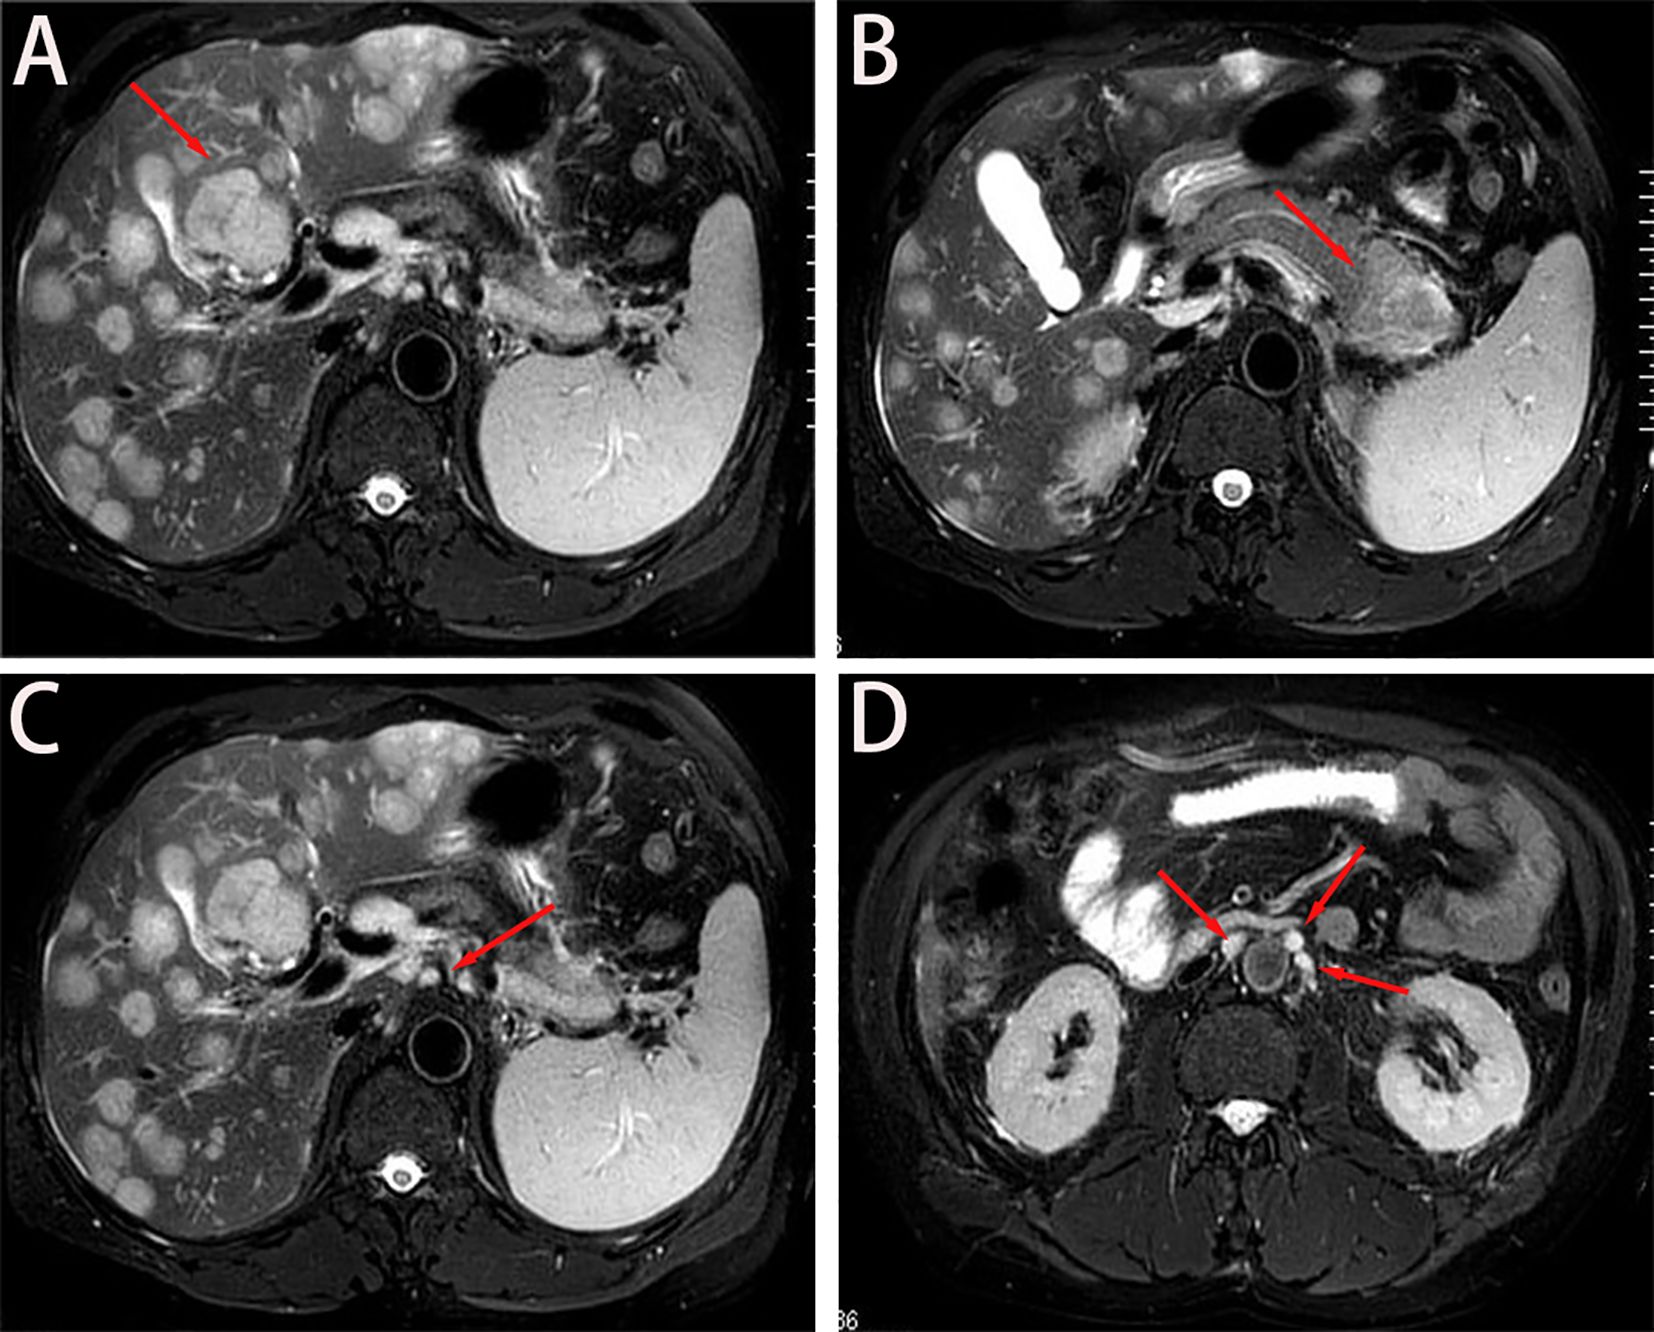

A 56-year-old male with well-controlled hypertension presented with a one-week history of epigastric pain and was admitted on July 12, 2024. Initial evaluation showed mild leukocytosis and elevated tumor markers (AFP: 9.22 ng/mL [normal: 0-8.7]; CEA: 78.4 ng/mL [normal: 0-7.2]). Contrast-enhanced MRI (July 14, 2024) identified a 4.7 × 3.7 cm malignant lesion in the pancreatic tail with synchronous hepatic metastases and hilar/retroperitoneal lymphadenopathy (Figure 1). Percutaneous liver biopsy (July 15, 2024) confirmed metastatic adenocarcinoma (Figure 2A), with immunohistochemistry showing CK7 (+), CK19 (+), HepPar-1 (–), HER-2 (1+), AFP (-), CA19-9 (-) and a Ki-67 index of 10% (Figures 2B–H). Molecular profiling revealed a high tumor mutational burden (TMB) of 54.05 mutations per mega base (TMB-H) (Figure 2J). The tumor was microsatellite stable (MSS) and lacked BRCA1/BRCA2, BRAF, and KRAS mutations. The patient was diagnosed with stage IVB PDAC (AJCC 8th edition) with TMB-H/MSS/KRAS wild-type features. The patient, with an ECOG performance status of 1 and adequate organ function, began quadruple therapy on July 20, 2024. The chemotherapy regimen included nab-paclitaxel (200 mg on days 1 and 8) combined with gemcitabine (1.4 g on days 1 and 8). Nimotuzumab was administered for targeted therapy at 400 mg weekly, while the immunotherapy component included cadonilimab at a dose of 750 mg every three weeks (Figure 3).

Figure 1. Baseline imaging findings of metastatic pancreatic adenocarcinoma. (A, B) Axial T2- weighted MRI demonstrates: (A) Diffuse hepatic metastases (arrows) with characteristic hyperintense signal; (B) A 4.7 × 3.7 cm² heterogeneously enhancing primary mass (asterisk) in the pancreatic tail. (C) Coronal view reveals metastatic involvement of the hepatic hilar lymph nodes (arrowheads), showing irregular margins and diffusion restriction. (D) Sagittal reconstruction identifies multiple enlarged retroperitoneal lymph nodes (circles) along the para-aortic region, consistent with metastatic spread.